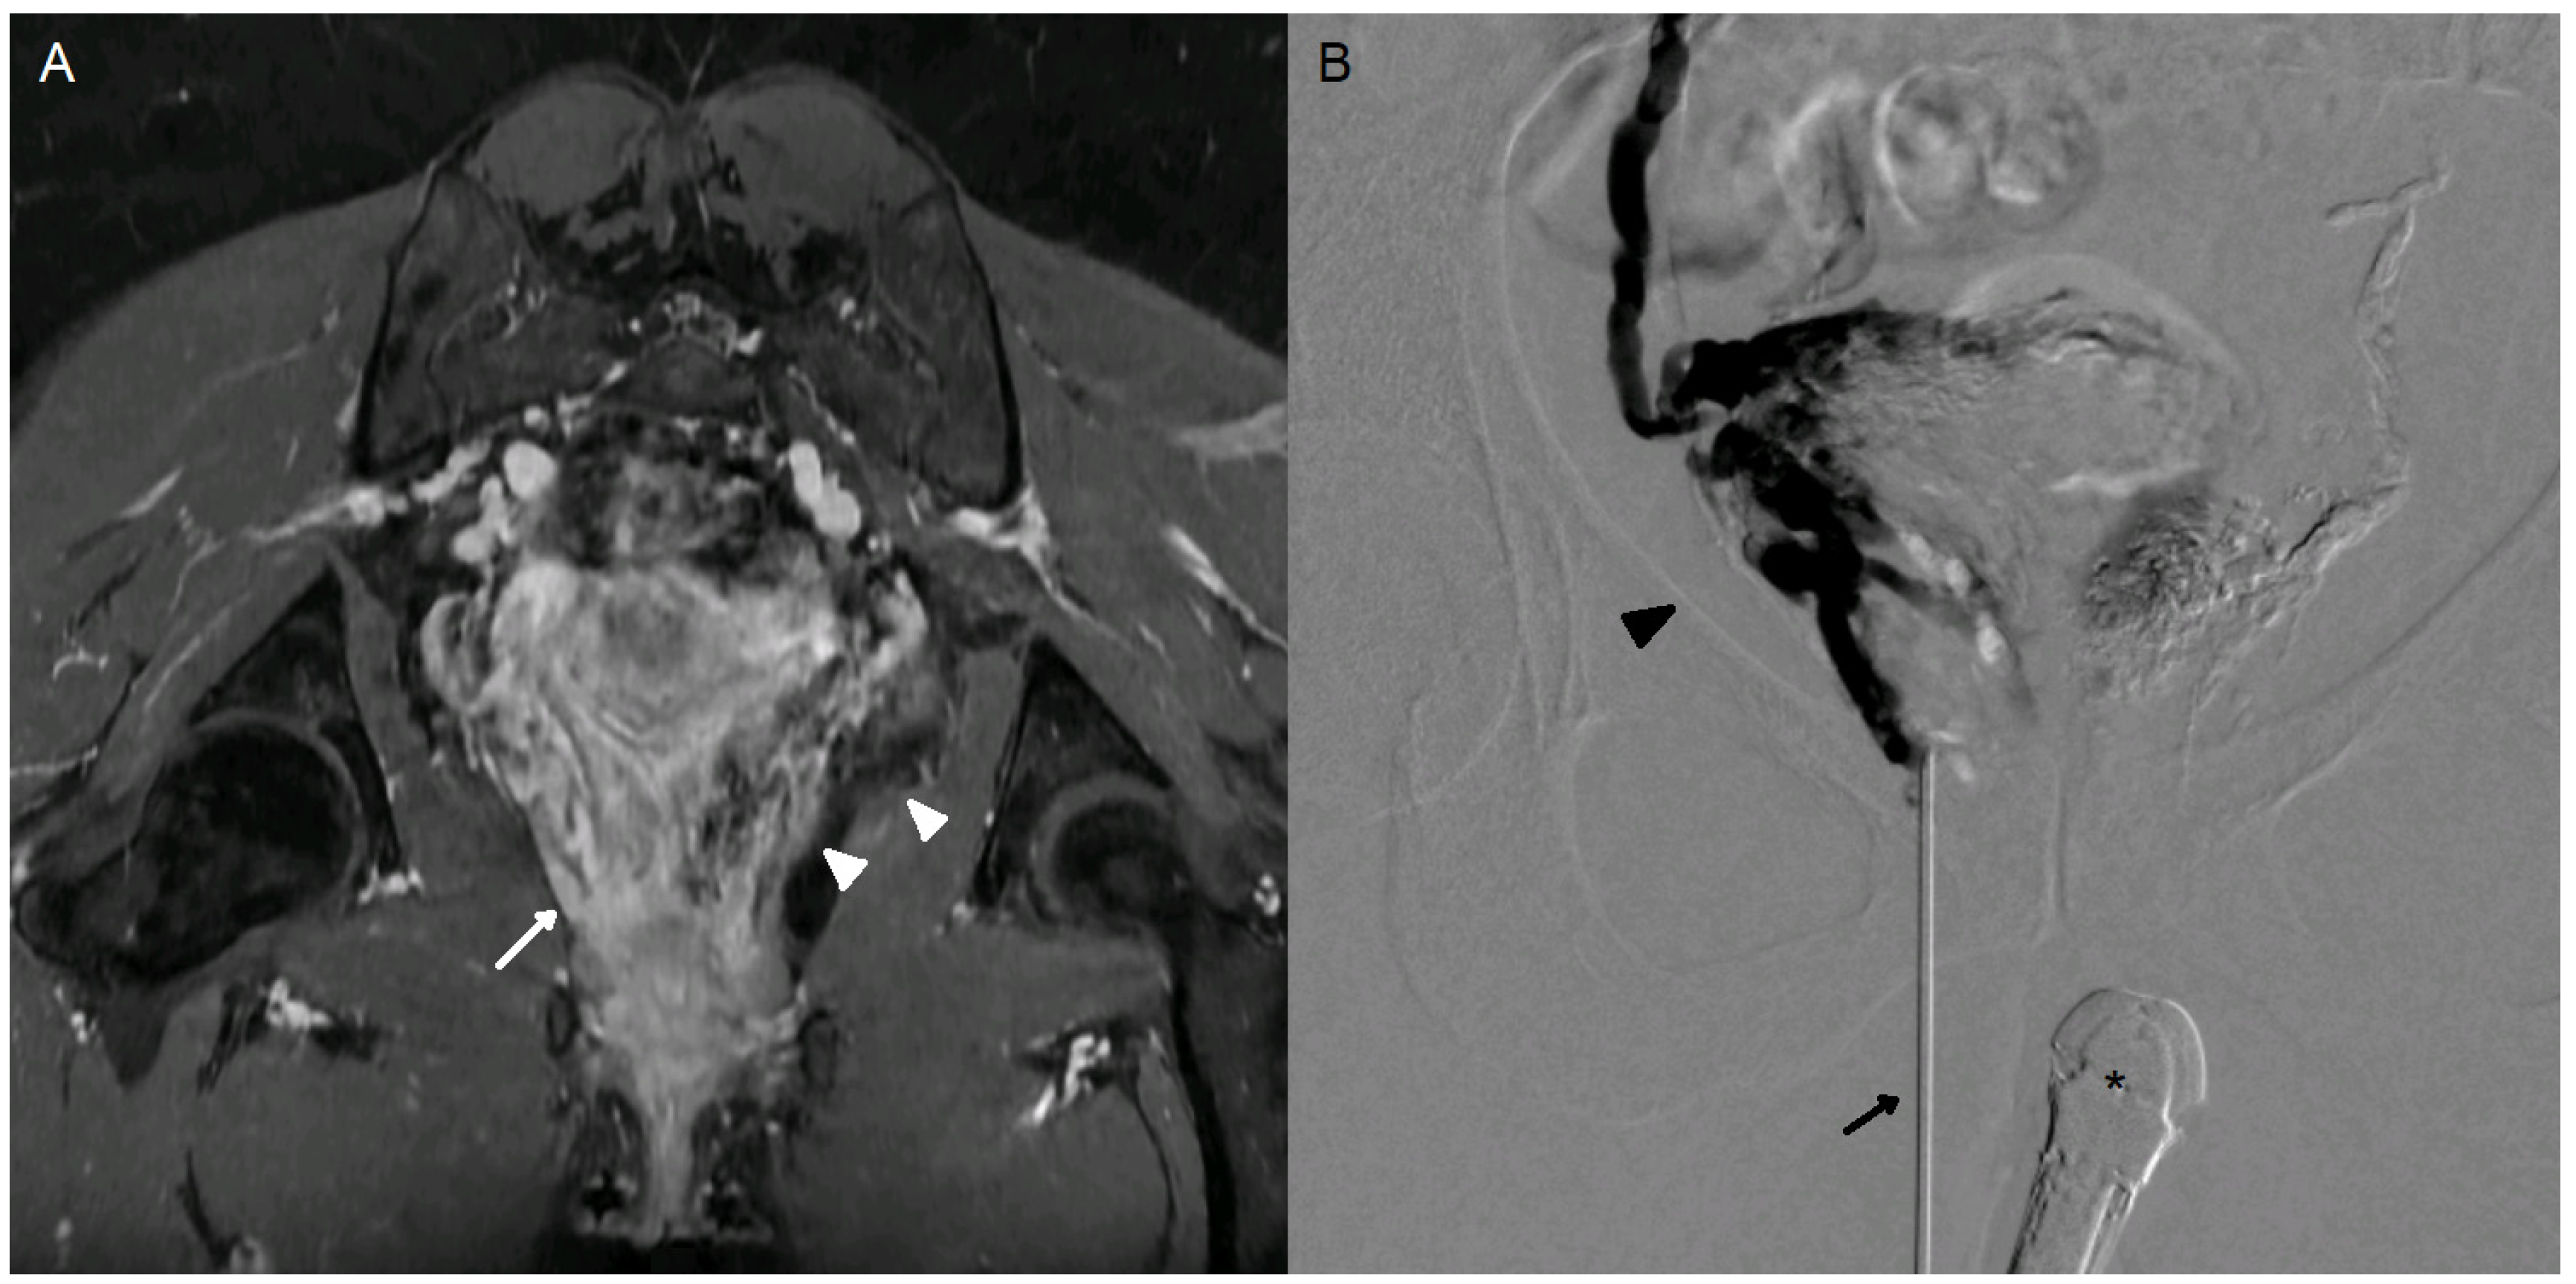

There were no major complication. One patient reported a minor complication consisting of transient dysuria, which resolved spontaneously in less than a week (1/10, 10%). Imaging follow-up showed a significant reduction in perivaginal varicosities in all cases (100%) (Figure 5).

Figure 5. Comparison of ultrasound and MRI images before and after embolization. (A) Visualization of perivaginal varicosities (*) on endovaginal ultrasound. Simulated needle trajectory (---). (B) Same ultrasound image immediately after embolization. Attenuation artifact from the embolic agent with posterior acoustic shadowing (white arrows). (C) Pre-embolization MRI. Coronal T2 STIR sequence through the uterine torus and vagina. Multiple bilateral peri-uterine and perivaginal varicosities appear hyperintense. (D) MRI at 3 months after embolization by endovaginal guidance. Coronal T2 STIR sequence at the same level. Marked reduction in peri-uterine and perivaginal varicosities. Embolization material appears hypointense within the veins (#). Persistent dilated left perivaginal varices, though the patient was asymptomatic (*).